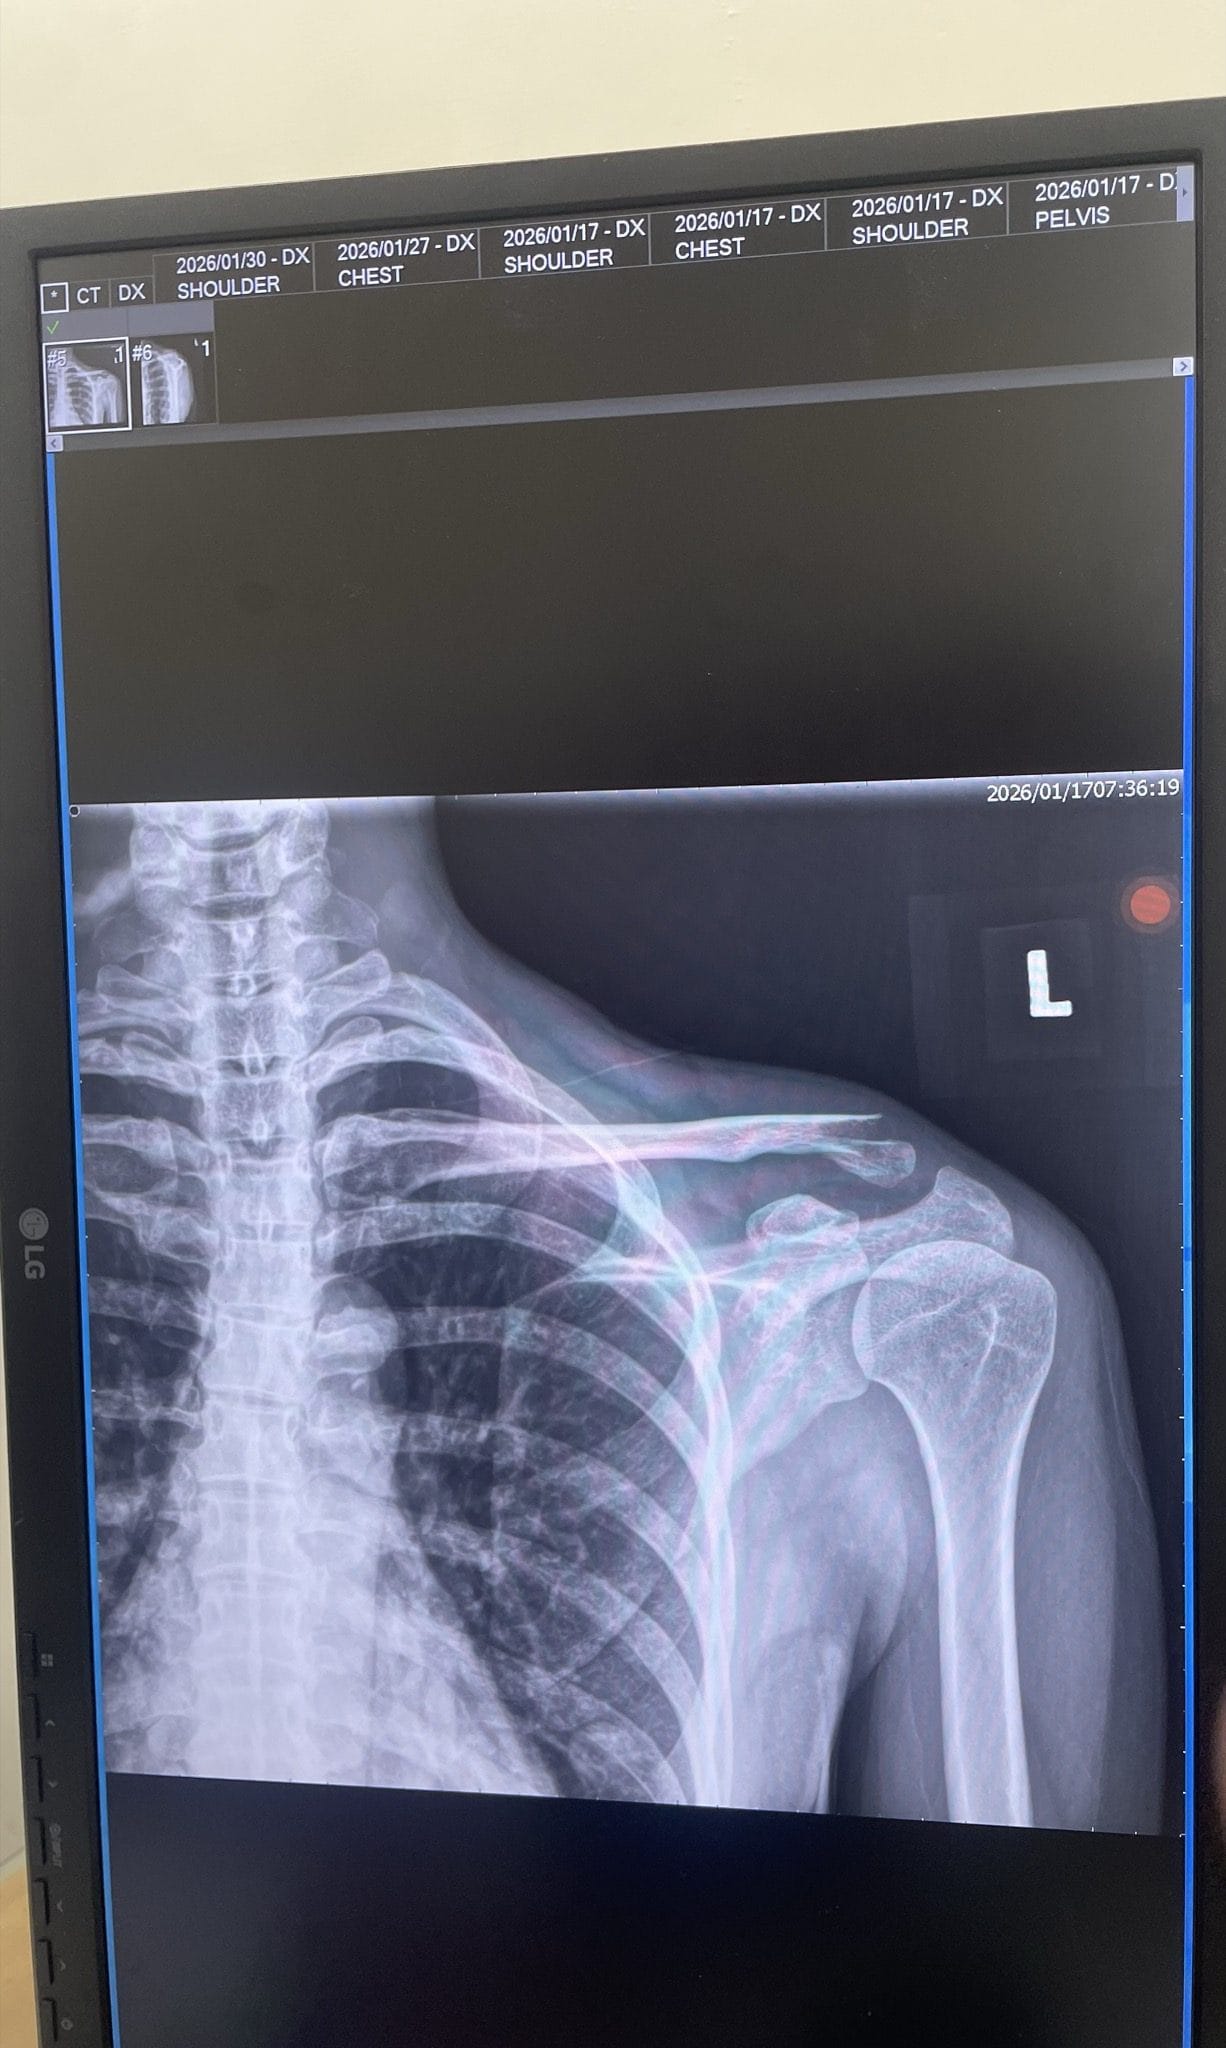

往下了解事件全貌 ↓民國 115 年 1 月 17 日,原告Doris參加東三塔自行車活動時,被告翁先生從後方切入車道,未保持安全距離,後輪撞上原告前輪,導致原告摔車,造成左側鎖骨骨折,緊急手術植入鈦金屬骨板,醫囑恢復需一年以上。

左側遠端鎖骨位移性骨折,手術植入鈦金屬骨板,恢復需一年以上

東三塔自行車挑戰活動,台2線 32.3K。原告左側鎖骨骨折,緊急手術植入鈦骨板。